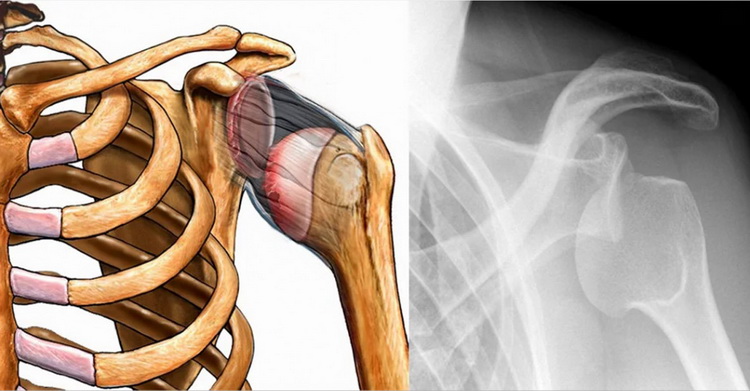

Плечевое сочленение является одним из наиболее подвижных и функционально значимых в опорно-двигательном аппарате человека. Его анатомическое строение, обеспечивающее широкий диапазон движений, одновременно предрасполагает к высокой уязвимости. Одной из наиболее серьёзных и распространённых травм этой области считается вывих плечевого сустава. Это патологическое состояние, характеризующееся стойким смещением суставных концов костей, образующих сочленение, с выходом головки плечевой кости из суставной впадины лопатки. Подобное повреждение влечёт за собой не только интенсивный болевой синдром, но и структурные нарушения, включая разрыв капсулы сустава и повреждение окружающих связок, сухожилий и мышечных волокон.